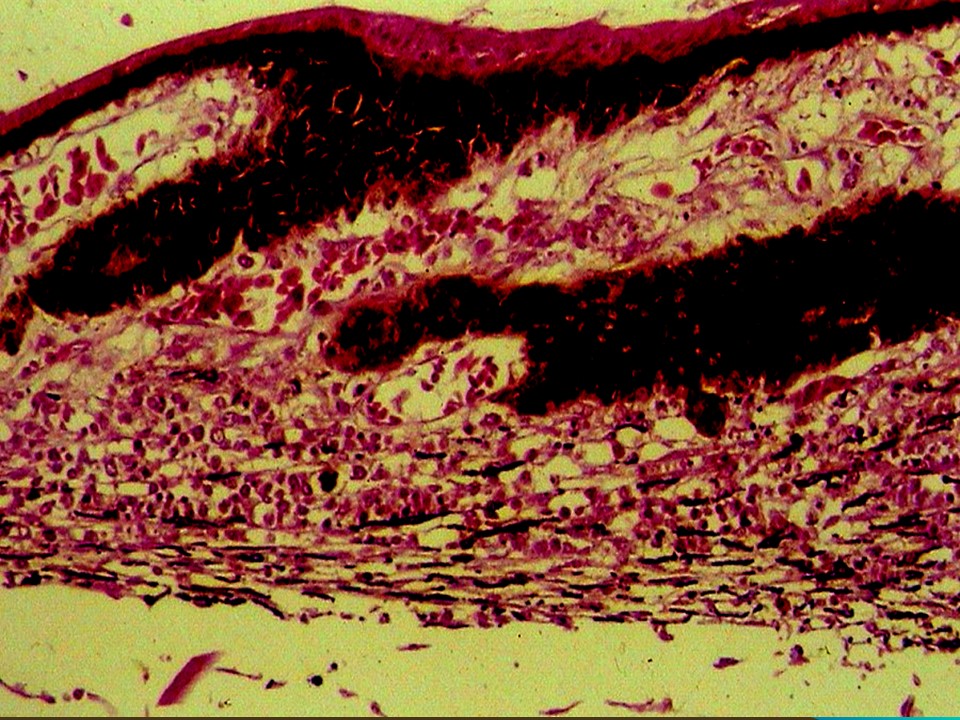

疾病中文名稱:馬立克病

疾病英文名稱:Marek's disease

影像說明:翼神經受侵犯而翅膀下垂,坐骨神經受侵犯呈劈腿狀